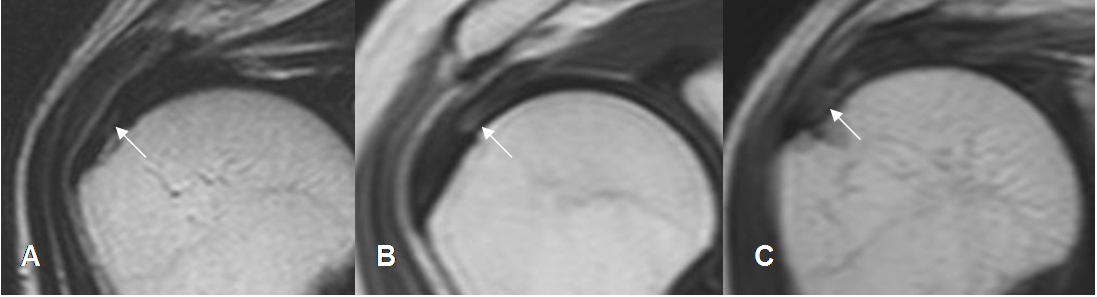

Fig 119. Ruptura parcial del supraespinoso.

A, B y C: RM coronal en T2. Diferentes grados de ruptura parcial del supraespinoso.

En A menor de 3 mm, B entre 3 y 6 mm y C, mayor de 6 mm.